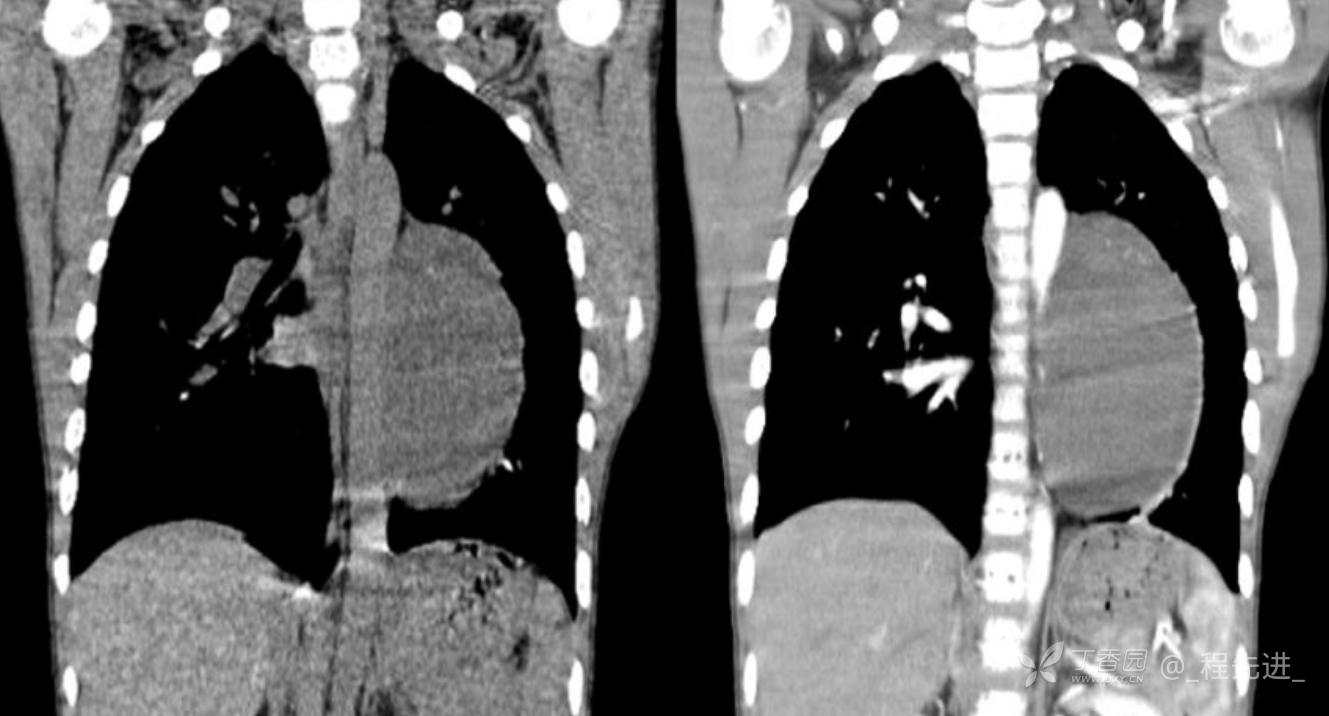

11月特别精彩病例|胸片示“左侧胸腔包裹性积液”,CT增强你诊断啥?【病理已公布】

呱呱叫了 等 3 位达人已点赞男,11岁,患儿因其爷爷近期在我院诊断“肺结核”,于外院行结核筛查,胸片示“左侧胸腔包裹性积液”,近期无咳嗽、发热、纳差、盗汗、乏力、胸痛、胸闷、气促不适,精神反应可,为求明确“左侧胸腔包裹性积液”病因,遂来我院门诊就诊,门诊以“胸腔积液查因”收住入院。发病以来,精神尚可食欲如常,大便如常,小便量如常,体重无明显变化